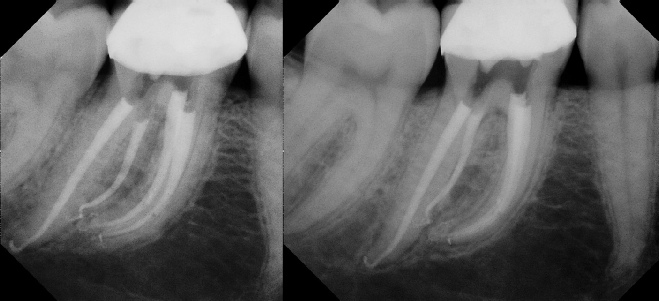

Root Canal Retreatment - Meriden 8 mos. recall Post-op Pre-op